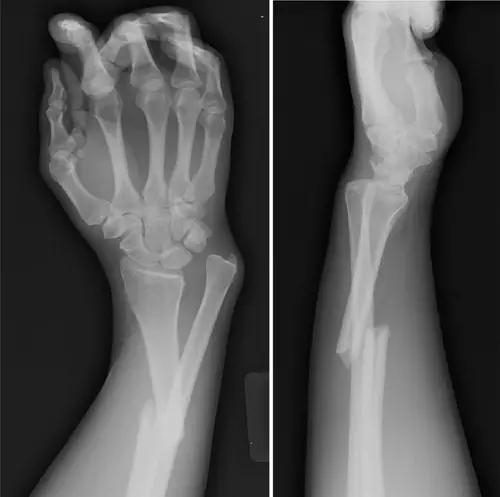

10. Galeazzi 骨折(盖氏骨折)

桡骨干下 1/3 骨折合并尺骨小头脱位。

盖氏骨折正侧位(来源:Orthobullets)